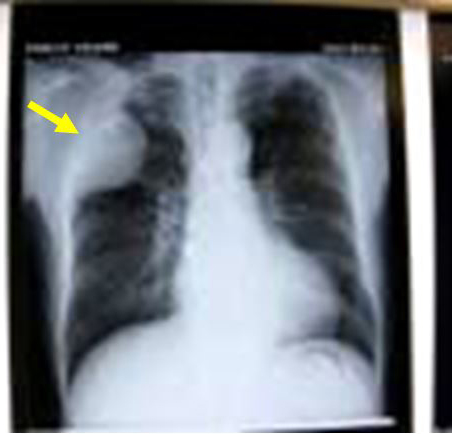

左肺癌の画像所見

胸部XP(左上肺野に腫瘤影あり)

(1)胸壁浸潤肺癌の術前・術後の胸部単純X線および術中写真です。手術は右肺上葉切除術+胸壁合併切除(右第2~6肋骨切除)+縦隔リンパ節郭清を施行しました(下図)。

術前 胸部XP